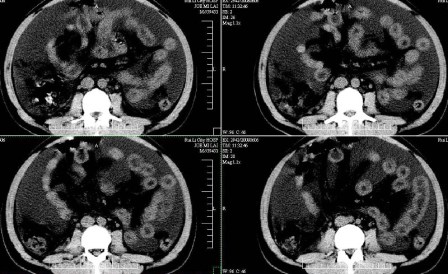

标题: CT13930:M,33岁,腹胀、腹痛10天余。 [打印本页]

标题: CT13930:M,33岁,腹胀、腹痛10天余。

右上腹压痛,肝大,质硬。腹水征。ct:肝右叶(后段)低密度影,性质待定。

肝硬化、大量腹水,肝右叶巨大肿块,境界欠清,中间见不规则低密度坏死区,考虑肝癌应该问题不大,至于肝左叶低密度灶是否转移应该意义不是很大了,慎重起见还是建议增强扫描。